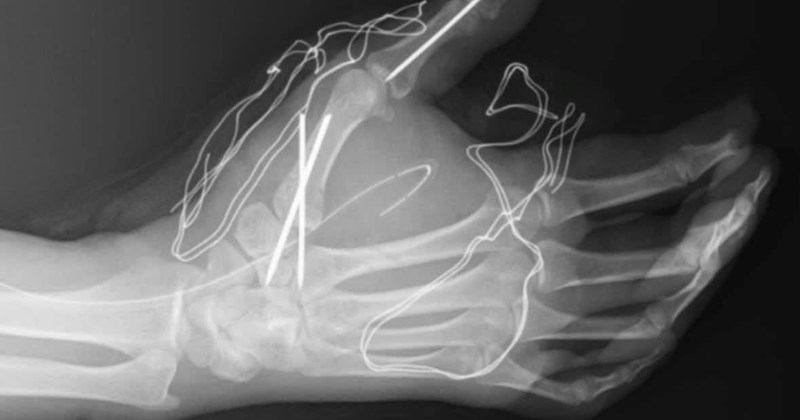

Sự việc xảy ra vào chiều ngày 27/1 tại Hà Nội, khi người thanh niên này đốt pháo tự chế Lao Động. Hậu quả là bàn tay của nạn nhân bị dập nát nghiêm trọng, cần phải nhập viện để điều trị.

Vụ nổ pháo đã gây ra những tổn thương nặng nề về thể chất cho nạn nhân Lao Động. Anh phải đối mặt với nguy cơ mất đi một phần hoặc toàn bộ chức năng của bàn tay.

Hiện tại, nạn nhân đang được điều trị tích cực tại bệnh viện Lao Động. Các bác sĩ đang nỗ lực để cứu chữa và phục hồi chức năng cho bàn tay của anh. Chính quyền địa phương chưa có thông tin về vụ việc.